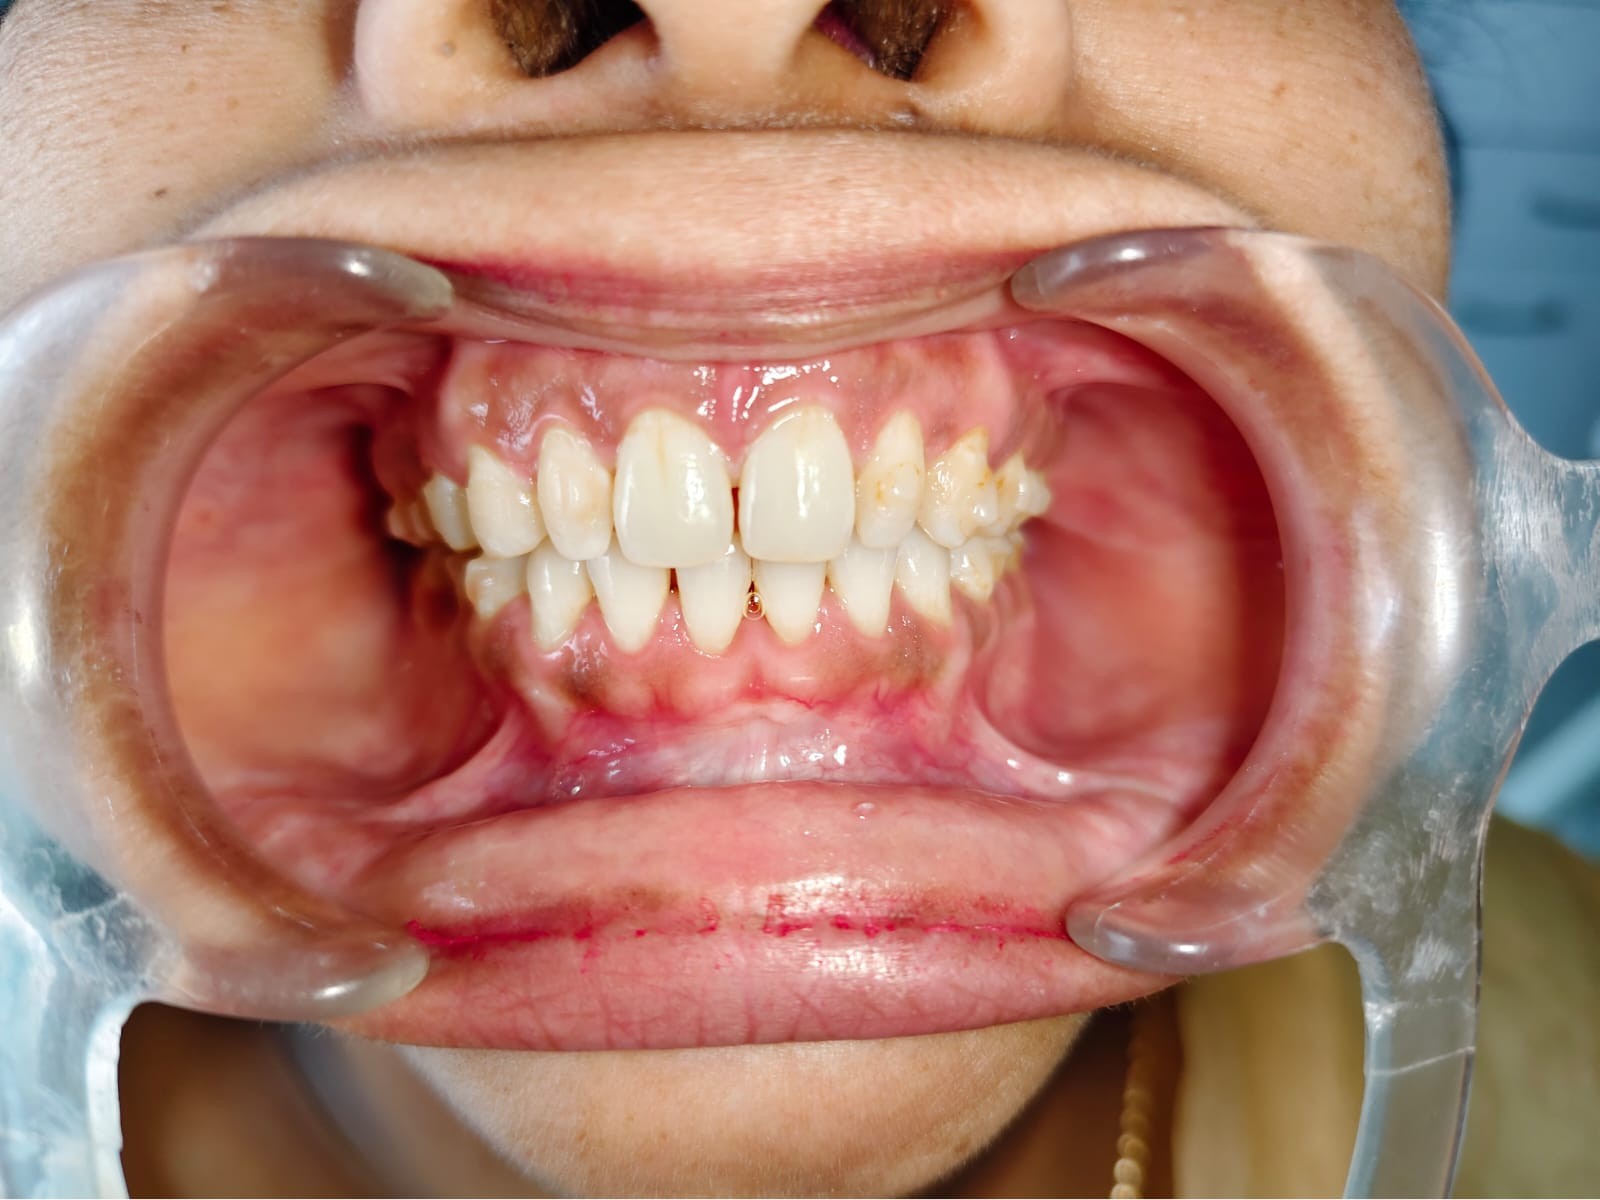

After/Before

See stunning smile transformation before and after

Before After